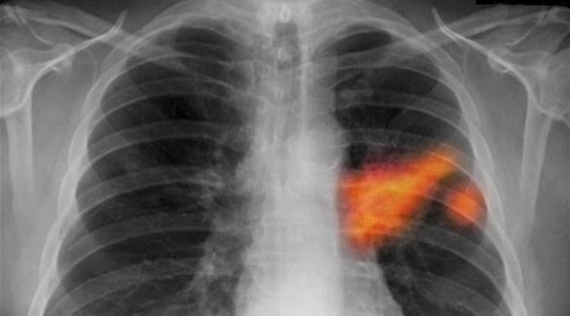

خبرني - قال علماء

إن سرطان الرئة يمكن أن يظل كامنا لمدة أكثر من 20 عاماً قبل أن يصبح مميتاً، الأمر

الذي يساعد على توضيح لماذا يصعب علاج هذا المرض الذي يودي بحياة أكثر من 1.5 مليون

شخص سنوياً في جميع أنحاء العالم.